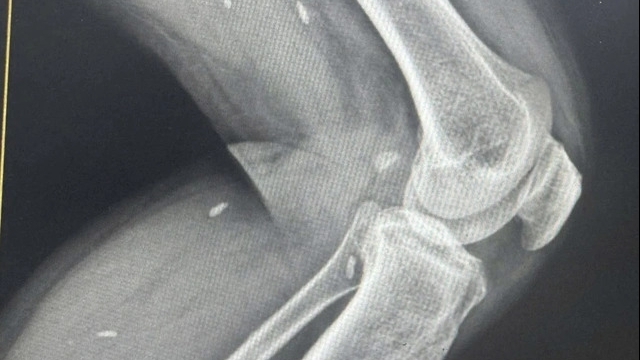

Ngay sau khi tiếp nhận, nam bệnh nhân này lập tức được cách ly, theo dõi và báo cáo với các cơ quan chức năng trong đêm giao thừa, tiến hành làm các xét nghiệm, chiếu chụp cần thiết.